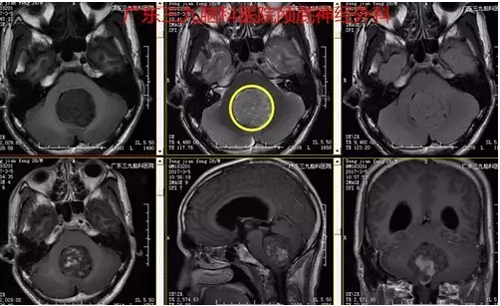

邓某,于2017年3月5日入院,患者诉2周前无明显诱因间断出现头晕头痛,通过相关检查,诊断:小脑蚓部占位性病变。完善术前检查,3日后行“小脑蚓部占位性病变切除术” ,术中肿瘤全切,术后恢复良好。术后诊断:小脑蚓部髓母细胞瘤。

图2:术前磁共振提示肿瘤位置、大小约4-5cm